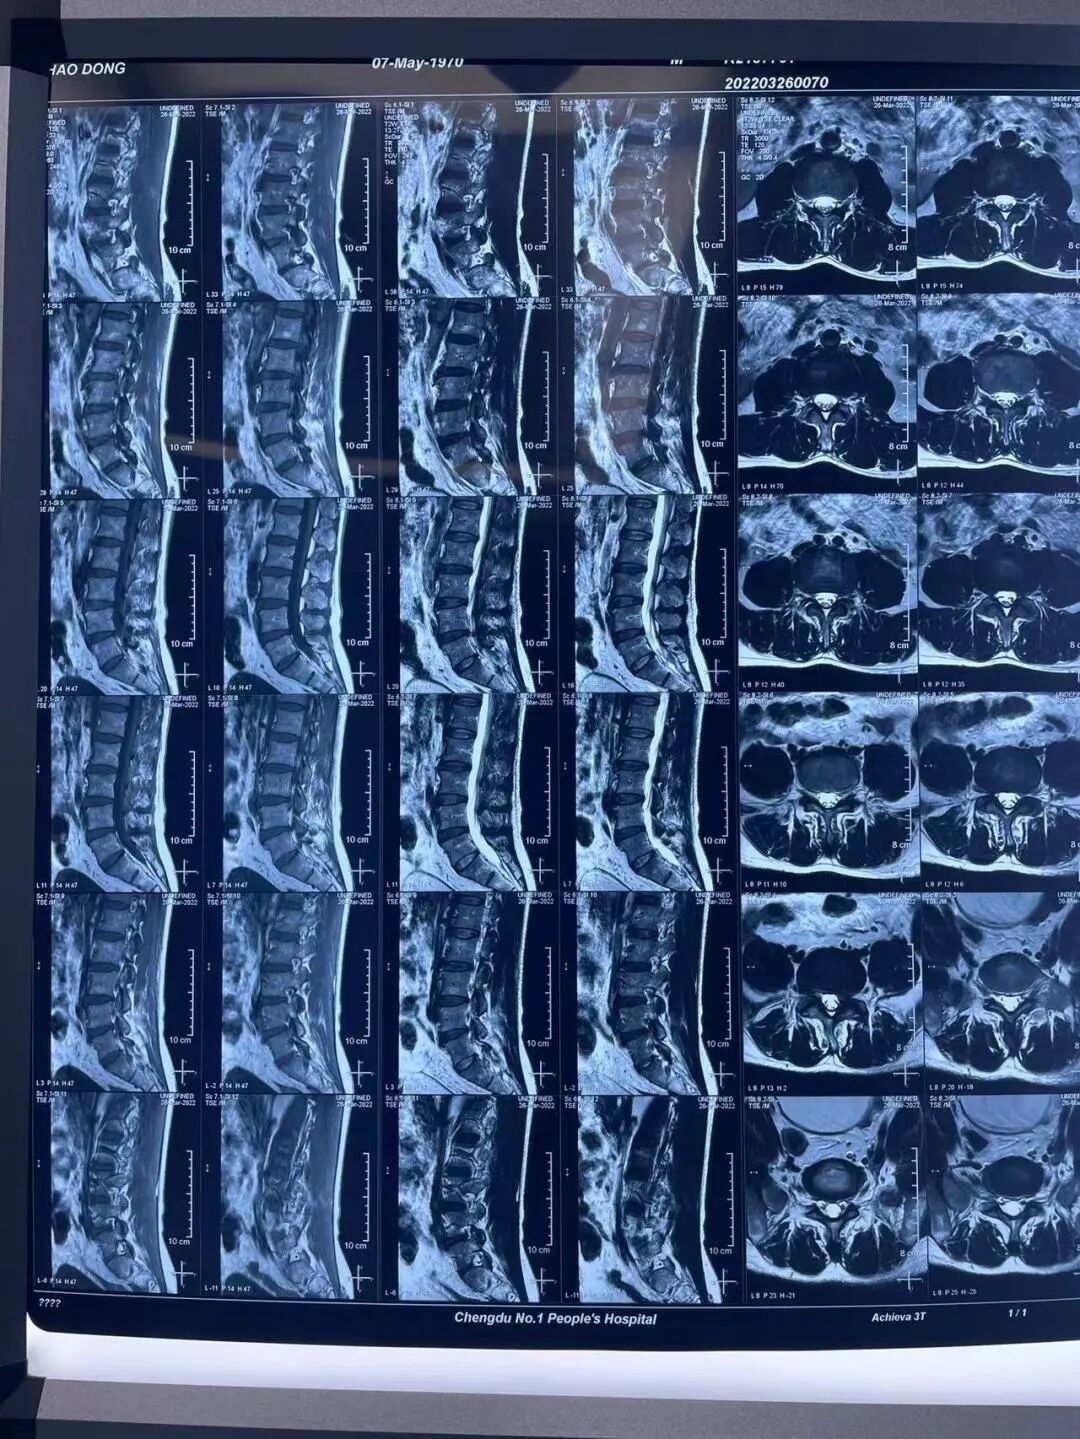

近期,李果教授为一五十一岁男性腰椎间盘突出患者成功实施L4-5节段椎间孔镜下髓核摘除+纤维环修复术,病例分享如下:

患者术前影像资料